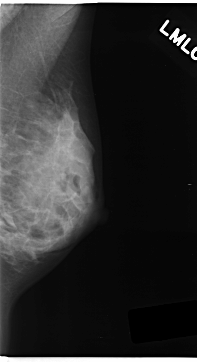

Digital Database for Screening Mammography

Volume: cancer_05 Case: C-0152-1

C_0152_1.LEFT_MLO

LEFT_MLO LINES 4704 PIXELS_PER_LINE 2552 BITS_PER_PIXEL 12 RESOLUTION 50 NON_OVERLAY

FILE: C_0152_1.RIGHT_MLO.OVERLAY

TOTAL_ABNORMALITIES 1

ABNORMALITY 1

LESION_TYPE MASS SHAPE LOBULATED MARGINS ILL_DEFINED

ASSESSMENT 5

SUBTLETY 3

PATHOLOGY MALIGNANT